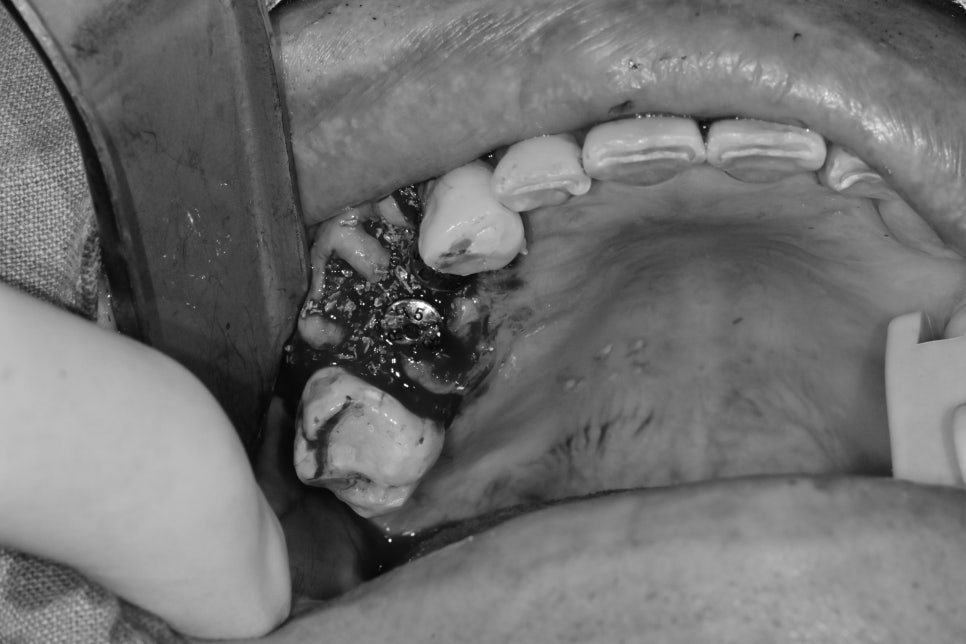

발치 후 해당 공간의 잇몸을 절개하여 수술을 하면

수술 시 시야 확보에는 도움이 될 수 있으나

치조골 이식술(뼈이식)을 했을 때

뼈이식재의 수술 부위에 고정력이 약해질뿐더러

기존 남아있는 치조골의 흡수가 일어날 수 있어

최대한 뼈이식 성공률을 높이기 위해

잇몸 절개 없이 수술을 했습니다

구내 사진에서는 해당 치아의 잇몸 쪽에 염증이 생겼다 없어졌다 하는 상태였습니다.

역시 초진 3D CT에서 치아를 감싸는 한쪽 벽을 이루는 뼈가 흡수되어

치아 뿌리가 노출된 상태에서 이 역시 발치 후 즉시 임플란트 식립 시

기존 잇몸을 차폐막으로 이용하여 치조골 이식술을 동반했습니다.